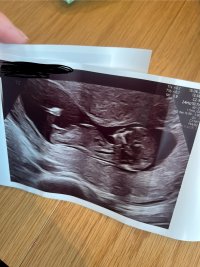

tipper du gutt eller er det noe i bildene som får deg til å tippe det?Nei, har egentlig ikke så altfor mye å gå etter. Noe med ansiktet, spisse/skarpe ansiktsdetaljer. Om en ser på hodefasongen ser det ut som jente (rundt) på ene bildet men så ser det ut som gutt (mere firkantet) på det andre bildet. Så det er vanskelig å si!Nei, enda litt over to uker tiltipper du gutt eller er det noe i bildene som får deg til å tippe det?

Vanskelig å se om det er nub man ser. , men ville tippet jente om jeg måtte gjetteNoen som vil gjette her?Vis vedlegget 467407

GuttNoen som vil gjette her?Vis vedlegget 467407

Jeg tenker også jenteNoen som vil gjette her?Vis vedlegget 467407

Det var jordmor sitt gjett også, men på fb mente de gutt! Tipper det har med at det ser ut som det er noe på «tuppen», men når jordmor analyserte så vi den fra flere sider og hun tenkte jente? Blir uansett gøy å finne ut hva som faktisk stemmer - kan oppdatere her inne etter OULJeg tenker også jente

Det er vinkelen på «tuten» som avgjør. Hvor langt var du på vei på ul?Det var jordmor sitt gjett også, men på fb mente de gutt! Tipper det har med at det ser ut som det er noe på «tuppen», men når jordmor analyserte så vi den fra flere sider og hun tenkte jente? Blir uansett gøy å finne ut hva som faktisk stemmer - kan oppdatere her inne etter OUL![]()